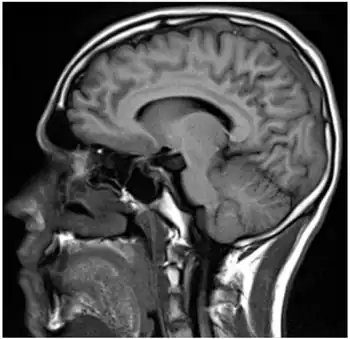

Sagital-Prothrombin G20210A as cause of cerebral venous thrombosis | |